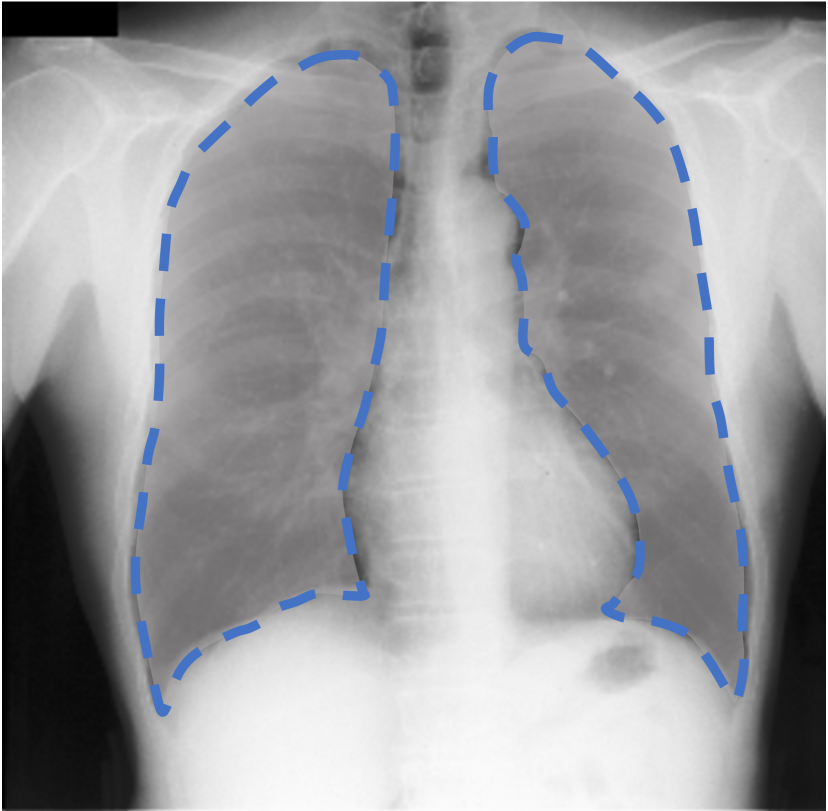

For each of these three datasets, we use three noise settings, denoted by , and . and are two settings synthesized by our Markov process with (expansion) and (shrinkage), respectively. Figure 4 shows examples of our synthesized label noise. We also include the mix of random dilation and erosion noise used by previous work (Zhu et al., 2019; Zhang et al., 2020b; a). This is achieved by randomly dilate or erode a mask with a number of pixels. Note that our Markov label noise can theoretically include this type of noise by setting . Detailed parameters for these settings are provided in the Appendix.

Real-world label noise. To evaluate with real-world label noise is challenging. We are not aware of any public medical image segmentation dataset that has both true labels and noisy labels from human annotators. Therefore, we use a multi-annotator dataset, LIDC-IDRI dataset (Armato III et al., 2015; Armato et al., 2011; Clark et al., 2013), and the coarse segmentation in a vision dataset, Cityscapes (Cordts et al., 2016). The LIDC-IDRI dataset consists of 1018 3D thorax CT scans where four radiologists have annotated multiple lung nodules in each scan. The dataset was annotated by 12 radiologists, and it is not possible to match an annotation to an expert. We use the majority voting as the true labels and the union of four annotations as noisy labels. We process and split the data exactly the same way as Kohl et al. (2018). Cityscapes dataset contains 5000 finely annotated images along with a coarse segmentation by human annotators that we use as the “noisy label”. We only focus on the ‘car’ class because (1) cars are popular objects and are frequently included in images; (2) the coarse annotation of cars is very similar to noisy annotation in medical imaging – they are reasonable distortions of the clean label without changing the topology. See Figure 4(c) for an example. The detailed settings of LIDC-IDRI and Cityscapes can be found in Appendix A.2.1.